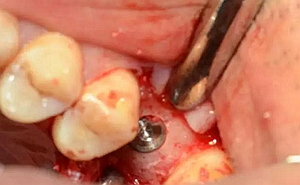

局麻后切開翻瓣

暴露骨面,輕柔處理軟組織

清理骨面和臨牙齦下結(jié)石及炎性肉芽組織

定點定向,初步擴孔

使用止停環(huán)控制深度,逐級預(yù)備打開嵴頂入路。探之竇膜力反饋正常,呈持續(xù)張力。手動探查分離通路周圍竇粘膜并略提升。

植入種植體,注意方向控制和初期穩(wěn)定性。

上覆蓋螺絲